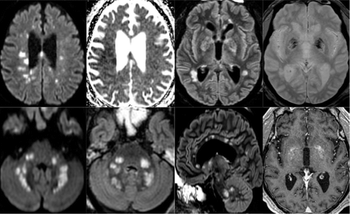

Cerebral infarction and hemorrhage are more common in severe cases while cranial nerve abnormalities affect patients with milder disease.

Clinicians should adopt a lower threshold for evaluating patients for stroke and providing care.